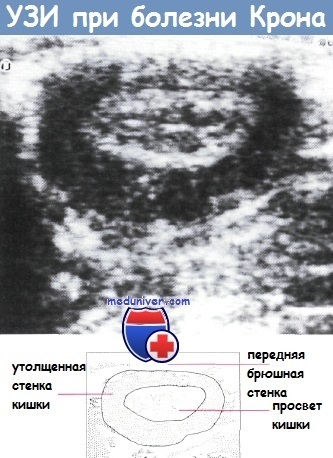

semne radiologice patognomonice ale bolii Crohn au, modificări pot fi cauzate de alte boli inflamatorii intestinale - tuberculoza, iersinioza. Diagnosticul se bazează pe o combinație de imagini cu raze X cu clinice, de laborator și tehnicile histologice. Atunci când este diagnosticată cu ultrasunete îngroșarea caracteristică a peretelui intestinal și modificarea răspunsului acustic al straturilor normale, se poate detecta zonele cu stenoza rd dilatarea anterioară. O astfel de cercetare este adesea neglijat, în ciuda faptului că oferă informații de diagnosticare valoroase, și poate fi utilizat pentru a identifica complicatii asociate, cum ar fi abcese.

b - o îngroșare a pereților intestinali două bucle (goale) săgeată. toroane inflamatorii in mezenterul intestinului subtire (săgeata lungă). benzi inflamatorii în mezenter seamănă cu pieptenele (scurt săgeată) și reflectă modificările vasculare și inflamații perilymphatic. Tomografie computerizată la nivelul crestelor iliace ale aceluiași pacient ca în figura (a).